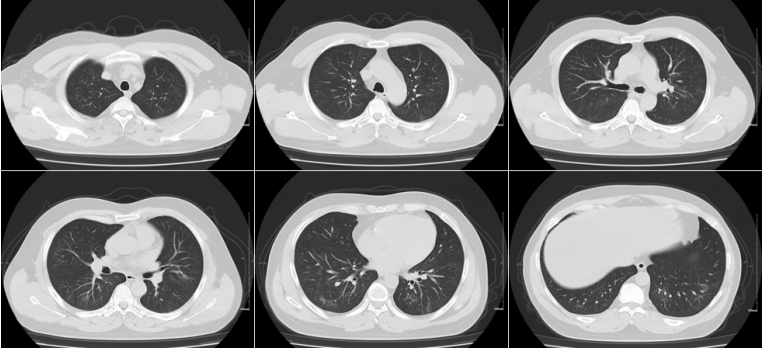

针对脓胸,血胸:多次胸腔留置粗管、细管引流胸水,引流液浓稠(图9),效果欠佳,患者体温仍有波动,复查胸部CT示左侧包裹性胸腔积液(图9)同时考虑左肺动脉瘤出血风险。5月13日行左胸腔镜下肺叶切除术、胸膜剥脱术、脓胸清除术。术中见:胸腔脓血性胸水,胸膜广泛增厚伴脓性纤维膜形成,肺同胸膜广泛致密粘连,左下肺见3个球型肿物,约3 cm大小,予分离胸腔粘连,吸除胸腔脓液,生理盐水冲洗胸腔,剥离脓性纤维膜及增厚的胸膜,切除左下肺叶,标本送检冰冻切片。

图片

9  胸腔引流液及胸部CT

5月23日复查胸部CT可见左肺下仍有部分胸腔积液没有引流12胸水化验:黄色,浑浊,有核细胞计数7226/μl,红细胞计数9000/μl,中性粒细胞百分率94%,淋巴细胞百分率3%,巨噬细胞百分率3%,利凡他试验阳性;胸水腺苷脱氨酶19.50 U/L,体液总蛋白定量16.8 g/L,体液乳酸脱氢酶1601 U/L,体液葡萄糖2.08 mmol/L。考虑患者反复发热可能与胸水引流不畅有关。

12  患者胸部CT(2025-05-23)